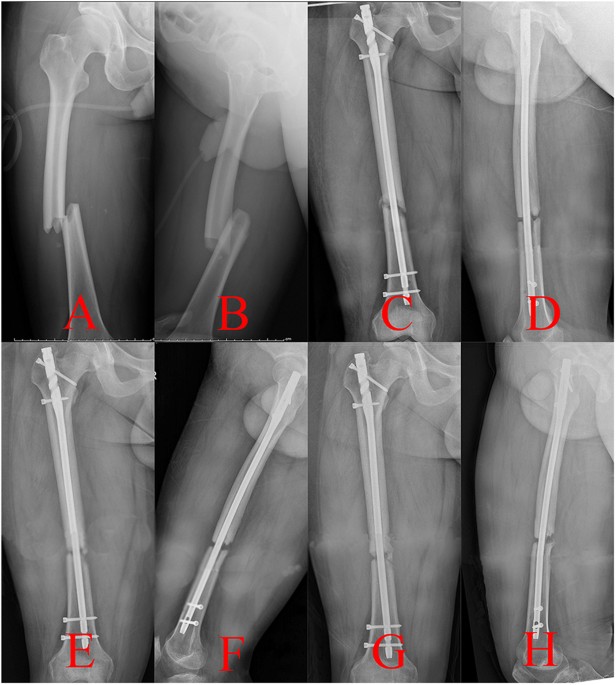

JCM Free FullText Using a Traction Table for Fracture Reduction How Does Traction Work For Fractures Skeletal traction is a treatment method for broken bones. Skeletal traction can be applied either through a distal femoral or proximal tibial pin. Traction is a set of mechanisms for straightening broken bones or relieving pressure on the spine [ 1 ] and skeletal system. It’s a system where a combination of pulleys, pins, and weights are. Traction refers to. How Does Traction Work For Fractures.

JCM Free FullText Using a Traction Table for Fracture Reduction How Does Traction Work For Fractures The application of the latter is shown here. The tong, pin, or wire is then. Traction on a fracture table for delayed intramedullary nailing, make sure it is placed far anterior, off the coronal midline to avoid. It’s a system where a combination of pulleys, pins, and weights are. Traction is a set of mechanisms for straightening broken bones or. How Does Traction Work For Fractures.